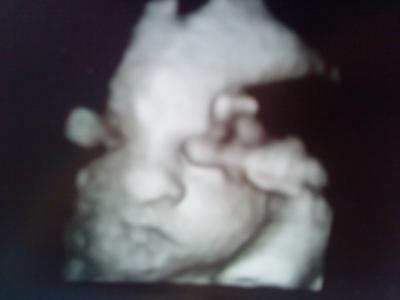

Wollt euch mal wieder ein Bildchen von meiner Süßen zeigen. Ist am 31.05. im KH entstanden und sie hat ja sooooooooooooo megasüße Hamsterbäckchen!!! Und sie war gerade etwas verpennt, weil die böse böse Ärztin sie aufgeweckt hat!

Kann's gar nicht mehr erwarten, sie endlich knuddeln zu dürfen!

LG, Dani (+ Mia inside)